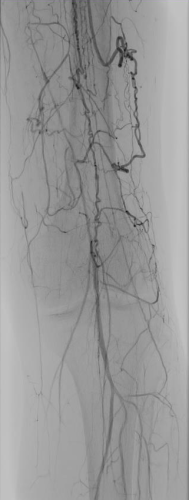

Results

Completion angiography demonstrated effective recanalization after use of Passeo™-18 Lux™ DCB, with normal flow to the plantar arch (Figure 2).